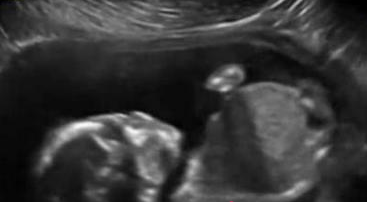

保健养生 子宫内胎儿自打脸 胎宝宝在孕妇肚中的小动作

子宫内胎儿自打脸,医生通过超声波检测仪,能够看到胎宝宝在孕妇肚中的小动作。近日,美国堪萨斯州,胎儿竟在妈妈子宫内打脸被抓拍到,连护士都称是第一次看到,感到很惊讶。

堪萨斯州女子凡妮莎怀孕......